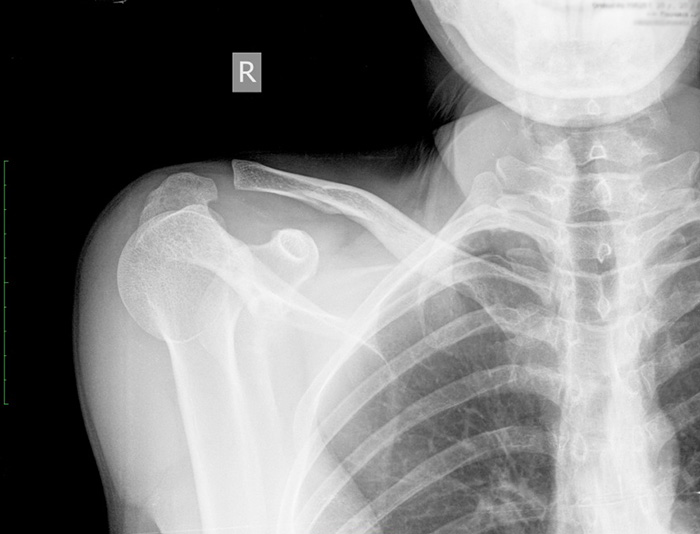

Некоторые травмы ключицы требуют немедленной медицинской помощи

Ключица входит в число костей, которые наиболее подвержены переломам. Её можно достаточно легко сломать или повредить, если приложить резкую силу к протянутой руке или плечу.

Как определить перелом ключицы?

Перелом ключицы обычно появляется вместе с травмой плеча. Боль в этой области, как правило, возникает внезапно и часто усиливается при попытке пошевелить плечом. При таких травмах человек может чувствовать трение и щёлкающий звук.

К другим симптомам перелома ключицы относится следующее:

- болезненность;

- отёки;

- гематомы в затронутой области;

- ограниченная подвижность руки.

Для диагностирования перелома ключицы врачи обычно применяют рентгеновское обследование после предварительного осмотра поражённой области. При осмотре медицинские работники задают пациенту вопросы относительно обстоятельств получения травмы, а также проверяют гематомы и отёки.